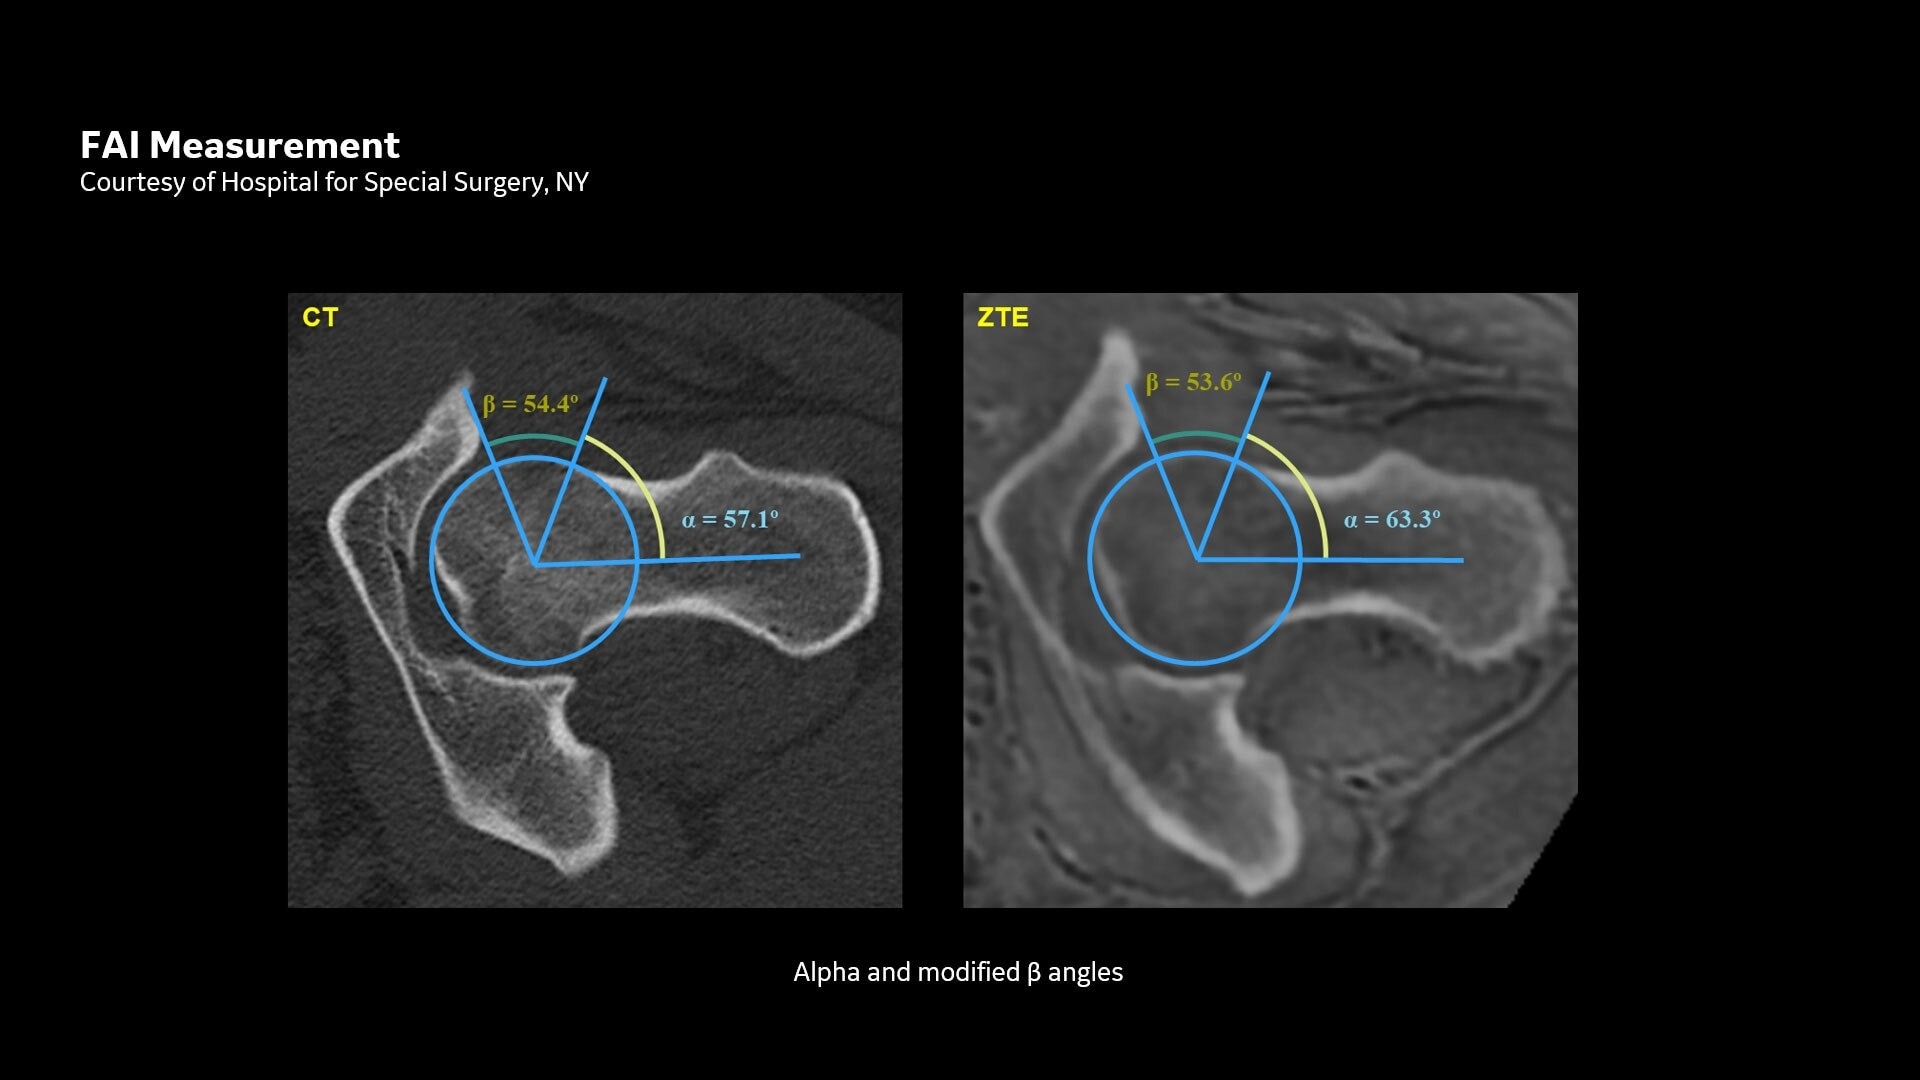

One-stop Orthopedic Shop

Provides cortical bone information co-registered with the soft tissue series

CT-like Image Contrast